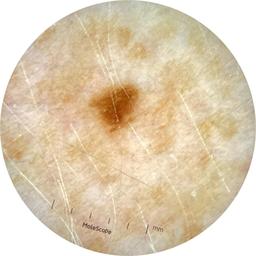

ISIC_9785574

image_type dermoscopic

lesion_id IL_0236417